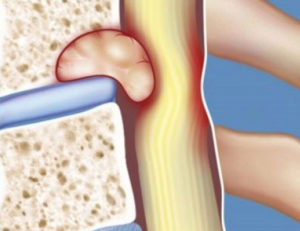

Развитие отека – это всегда реакция на какие-либо патологические процессы, происходящие в организме человека. Отек развивается чаще всего в том случае, если под воздействием каких-либо негативных причин разрушаются костные балки позвонков и повреждаются кровеносные сосуды. Чаще всего это своеобразная защитная реакция организма на какое-либо воздействие извне.

Травматизация тканей и сосудов приводит к тому, что развивается активное местное воспаление. Оно обычно протекает без присоединения инфекции, но в его результате образуется экссудат, который и провоцирует увеличение объема тканей. Экссудат призван помочь тканям адаптироваться к неблагоприятному воздействию, но иногда его бывает так много, что это сказывается на состоянии человека негативно.

- Различные травматические повреждения, особенно трабекулярного типа (происходит повреждение сосудов с образованием кровоизлияния, из-за которого и формируется воспалительный процесс).

Отек тела позвонка приводит к сдавлению спинного мозга и нарушению циркуляции спинномозговой жидкости (ликвора), которая протекает также через желудочки головного мозга.